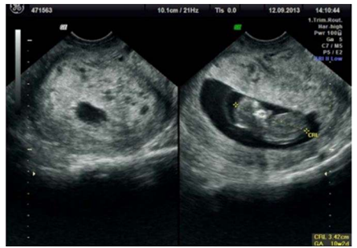

Paciente de 27 anos, G2P1A0, comparece à consulta de

pré-natal com 10 semanas de gestação pela data da

última menstruação, trazendo o exame de

ultrassonografia transvaginal mostrado na imagem.

Relata episódios de sangramento vaginal leve e

intermitente nas últimas duas semanas. Ao exame físico,

apresenta altura uterina maior que o esperado para a

idade gestacional e beta-hCG quantitativo com valores

acima do percentil 95 para a idade gestacional.

Descrição da imagem: Útero em AVF, presença de saco gestacional normoimplantado com embrião único medindo 3.42 cm o que corresponde a 10+2 semanas gestacionais com BCF detectável. Placenta com múltiplas formações císticas/vesiculares sugestivas de doença trofoblastica gestacional.